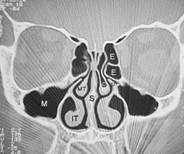

Da man sich als Laie schlecht vorstellen kann wo genau diese Nasenmuscheln in der Nase sitzen hier zusätzlich zu dem oberen Bild ein frontaler Querschnitt durch das Mittelgesicht:

Abb. 1   Abb. 2

Abb. 1: Hier relativ normale Verhältnisse. Die Nasenmuscheln lassen noch genügend Luft (schwarz) durch die Nasenhöhle strömen obwohl die Scheidewand leicht verkrümmt ist

Abb. 2: Auf der rechten Seite des Bildes sehen sie verdickte untere Nasenmuschel und seitlich daneben die Kieferhöhle (M). Die Nasenatmung ist hier einseitig stark eingeschränkt. Die dünnen schwarzen Linien stellen die noch verfügbare Nasenatmung links dar!

Erklärung: Schwarz: Luft, Graustufen: Weichteile, Weiß: Knochen, IT: untere Nasenmuschel, M: Kieferhöhle, S: Nasenscheidewand